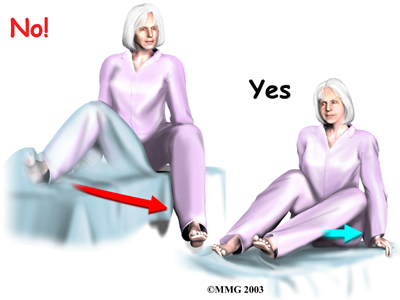

- Don't bend the hip past ninety degrees. This means do not lean too far forward when sitting up in bed.

Also, raising your knee up in bed can cause the hip angle to go past ninety degrees.

To avoid bending past ninety degrees when sitting in a chair, lean back slightly.

- Don't bend over past ninety degrees at the waist. Your hip may go past ninety degrees if you bend over at the waist to tie your shoes or pick up items off the floor.

Instead, use a reacher to put on your shoes and socks or to pick up items from the floor.